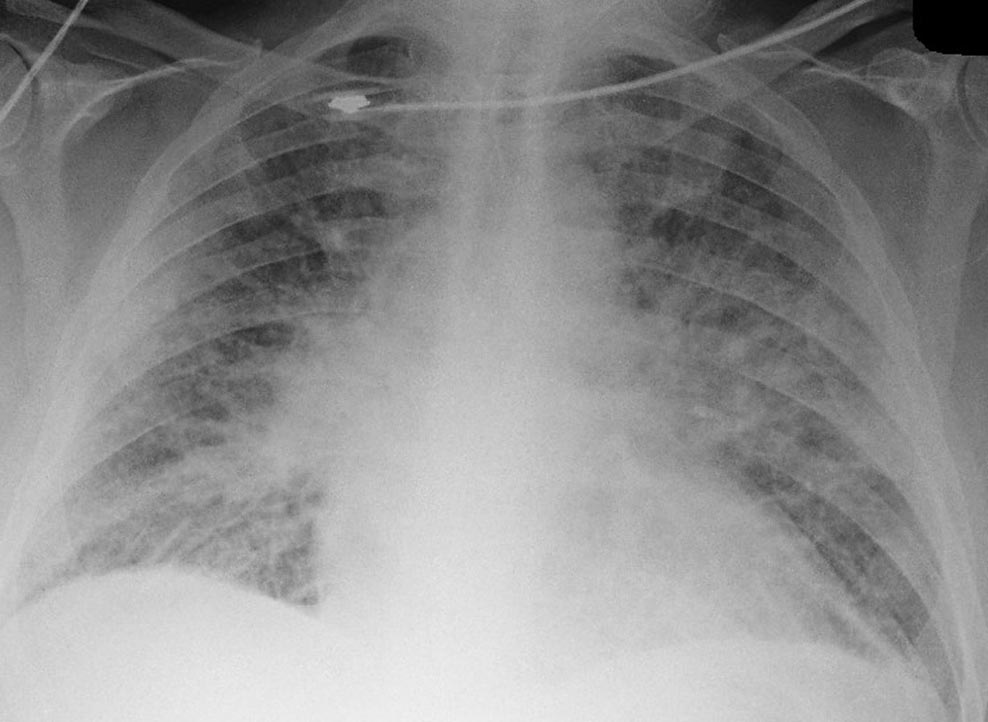

55 yo M presents to the Emergency Department with progressive shortness of breath and lightheadedness for one day. At arrival he is found to be hypotensive with signs of cardiogenic shock. EKG shows ST elevations in inferior leads. Learners should incorporate US as part of the assessment of this hypotensive patient and be able to resuscitate this patient in cardiogenic shock from underlying inferior MI.